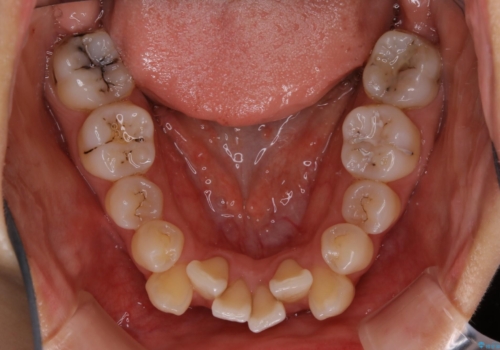

- 以前からコンプレックスだった八重歯の治療を主訴にご来院されました。

検査の結果、抜歯をすることでスペースを作って並べる方法が選択され、ワイヤー装置を用いた治療を開始することとなりました。

奥歯の上下のズレ等は軽度で、必要なスペースと抜歯により作られるスペースがほぼ等量だったため治療の単純化が計れ、大きな移動・見た目の劇的な変化に対して比較的早期での治療完了となりました。

叢生の度合いが重く、抜歯が必要なケース。八重歯の部分以外には大きな問題は認められなかったため、劇的変化が起こる治療でも比較的短期間で終了することができました。